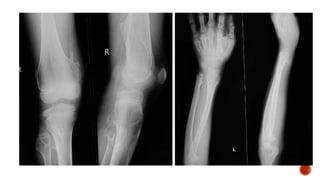

 AP and lateral radiographs of the skull show multiple tiny lucent areas with areas of

sclerosis in between, giving rise to salt and pepper skull appearance.

 Radiographs of both the legs, knees and left humerus show diffuse osteoporosis with

few well defined lytic areas.

 Radiograph of the hand shows osteoporosis with coarse trabeculations of the

phalanges with mild erosions along tteh radial aspect.

 Osteopenia

 Subperiosteal resorption: classically along radial aspects of phalanges